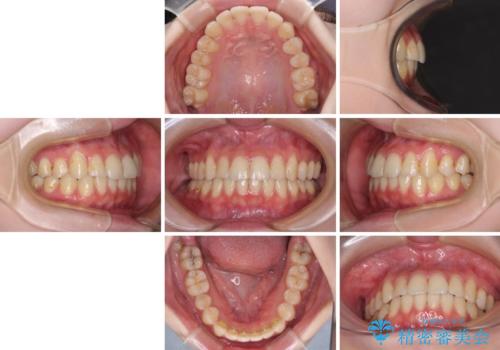

軽度な後戻りをインビザライン・ライトで改善

- 上下前歯のデコボコを気にして来院された患者様です。

以前矯正をした後戻りということで、歯列不正はそれほど大きくなかったため、インビザライン・ライトを用いて矯正治療を行うこととしました。

前歯のデコボコが残っており、シミュレーション通りに動いていない部分がありましたが、再矯正であることやご本人の満足いくところまでデコボコが改善されたとのことで、治療を終了することとしました。